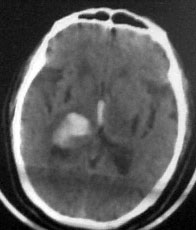

病人男性52岁,一年前曾患脑出血.今突发剧烈头痛,恶心,呕吐..病人家属说病人自去年脑出血以后,精神异常!请大家看看左侧颞叶病灶考虑什么?片子不是很清楚请大家见谅!!左颞叶病灶ct值最高处为85hu

左侧颞叶海马回钩部斑片状高密度致密影,考虑:出血.

病人此次症状应与右侧丘脑及基底节出血破溃入脑室有关。

左颞叶病灶我认为不是出血,就算是出血,也与右侧病灶性质不同。理由:1.该病灶密度较淡而不均匀,其间见斑点状更高密度。急性出血,应该不会是这个样子。

2.病灶对周围无推移挤压迹象,也无水肿。倒是病灶旁边、左侧环池局部扩张,与右侧病灶

完全不一样。

综合上诉特点,左颞叶病灶我首先考虑:avm。

左侧颞叶考虑血管畸形,右侧丘脑及基底节出血破溃入脑室

考虑1海绵状血管瘤。2脑膜瘤待排。建议增强

左颞叶病灶我认为不是出血,因为边界不清,无水肿带,应该是散在钙化灶,不排除avm,建议增强.

左侧颞叶病灶密度不均,似见点状钙化,支持血管畸形性病变.右侧病变为出血.